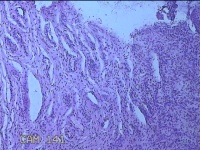

宫颈6点、12点组织

性别

女

年龄

33岁

临床诊断

人乳头瘤病毒感染

一般病史

发现HPV18,其他12种阳性近一月。

标本名称

大体所见

1.“宫颈6点组织”:灰白粉红色组织0.5x0.3x0.2cm一块。 2.“宫颈7点组织”:灰白暗红色组织0.8x0.3x0.2cm两块。

图1